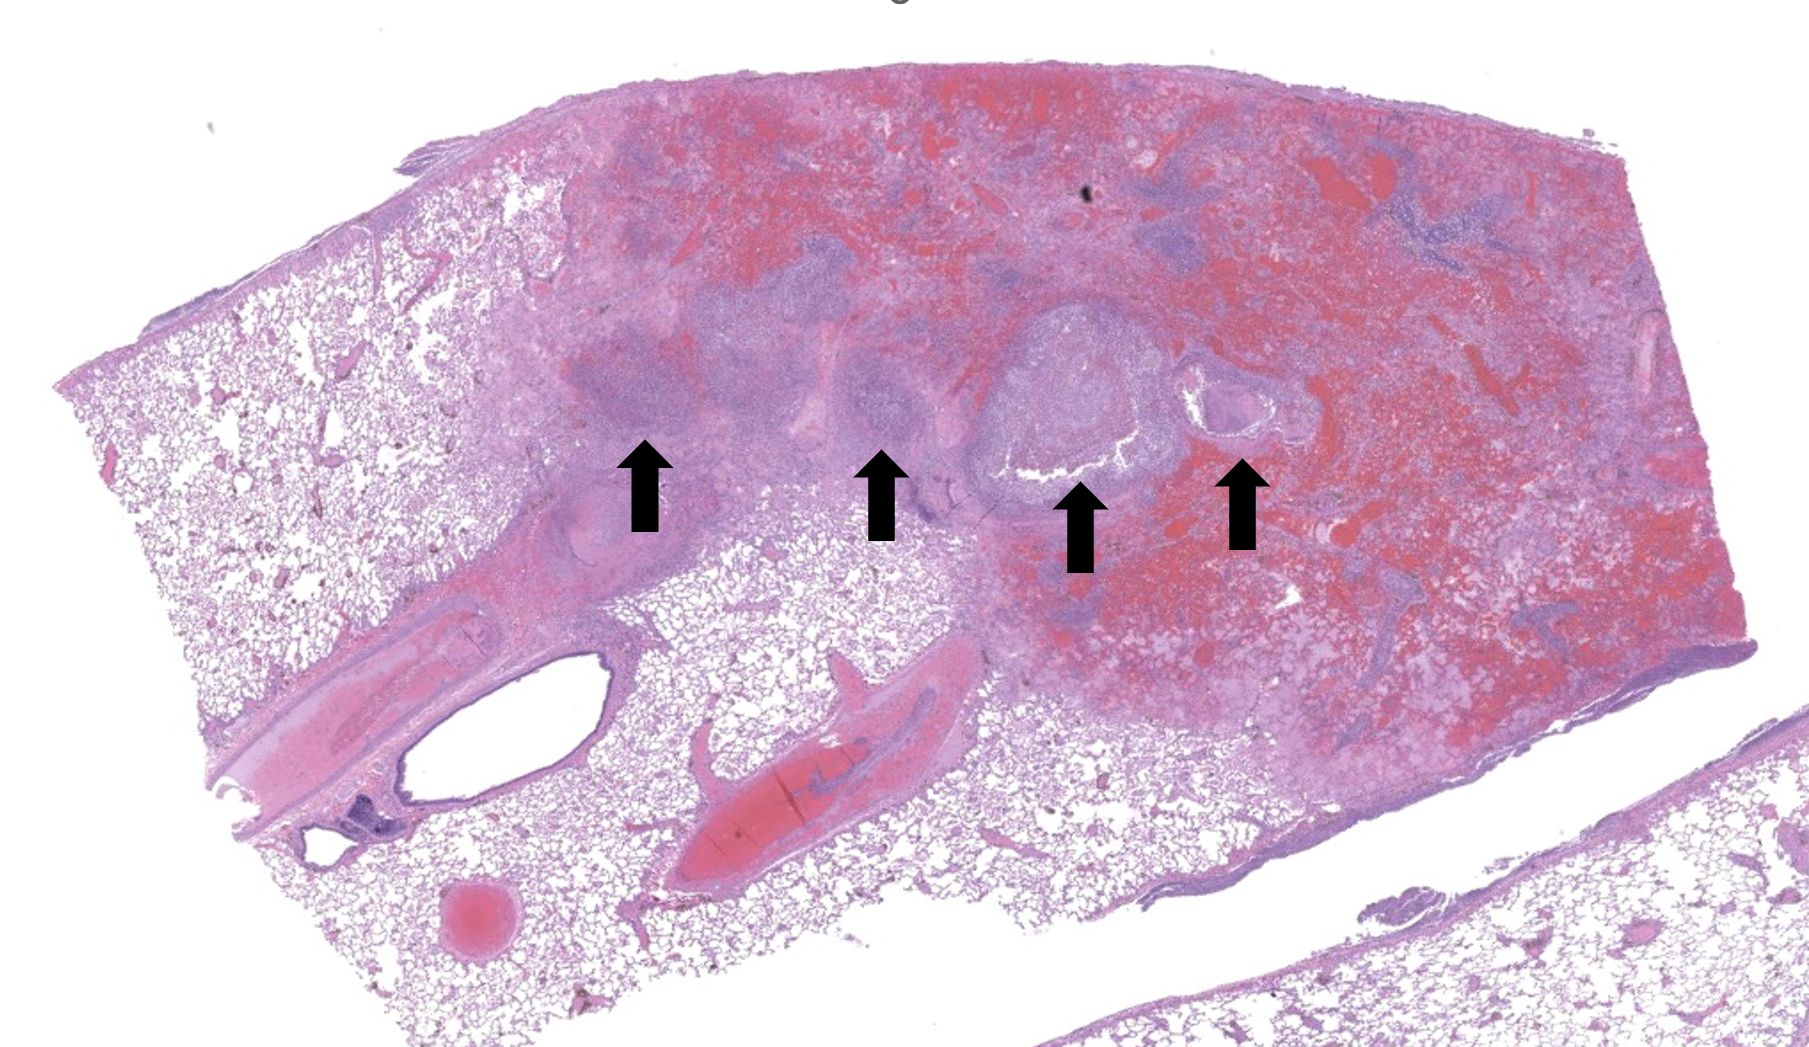

Regionally, sharply demarcated areas of the pulmonary parenchyma are markedly necrotic and replaced by abundant hemorrhage, fibrin, inflammatory infiltrates composed mainly of neutrophils and macrophages, and necrotic cellular debris. In these areas, multiple blood vessels contain thrombi consisting of large numbers of degenerate neutrophils, organizing fibrin, occasional colonies of bacterial coccobacilli, and necrotic cellular debris that variably obscure the lumen and vessel walls. Affected vessels often have smudgy, hypereosinophilic walls that are transmurally infiltrated by neutrophils, lymphocytes, and macrophages. In less affected regions, the alveolar spaces contain a small amount of fibrin, numerous foamy alveolar macrophages (some of which contain brown granular hemosiderin pigment), and fewer neutrophils and erythrocytes. There are moderate numbers of hemosiderin-laden macrophages mostly concentrated around pulmonary arteries, multifocally. Regionally, along the pleural surface there is a large amount of fibrin admixed with numerous degenerate neutrophils and necrotic cellular debris. The pleura itself is mildly thickened by fibrous connective tissue and edema and is multifocally lined by markedly reactive mesothelium, characterized by plump, rounded mesothelial cells.

Heart, right atrioventricular valve: Marked, chronic, fibrinosuppurative valvular endocarditis with intralesional bacterial colonies; Mild, multifocal, suppurative epicarditisLungs: Marked, regional, suppurative, necrotizing embolic pneumonia with vascular thrombosis and intrathrombotic bacteria; Marked, regional, fibrinosuppurative pleuritis

2. Lung: Pneumonia, embolic, necrotizing and suppurative, chronic, multifocal to coalescing, severe, with septic arterial thrombi and suppurative pleuritis.